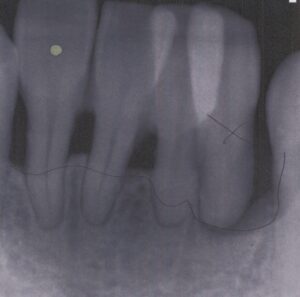

初診日 2016. 12.  (5年経過症例)

1年前から他の歯科医院にて部分的な治療を受けたが、どんどん歯が悪くなって、見た目が良くない・噛めないとのことで再治療を希望された。昨日、上の前歯が自然に取れた、他の医院に行こうとしたところ知人に当医院を勧められ来院した。アングルクラスⅡであった。

治療法

全顎的に歯周病が進行し、ほとんどの歯に動揺が見られた。アングルクラスⅢで下顎前歯部に叢生が見られ、全顎の再生療法の後に、全顎的にオールセラミッククラウンを装着し、既存の被せのやり直しを行なった。

審美的な仕上がりで、患者自身も満足した。5年経過し良好である。

現在は2〜3ヶ月おきのメインテナンス中である。

治療を行う上での 注意点 (リスク・副作用)

オールセラミックには欠け易いといったリスクがあるためナイトガードは必須である。